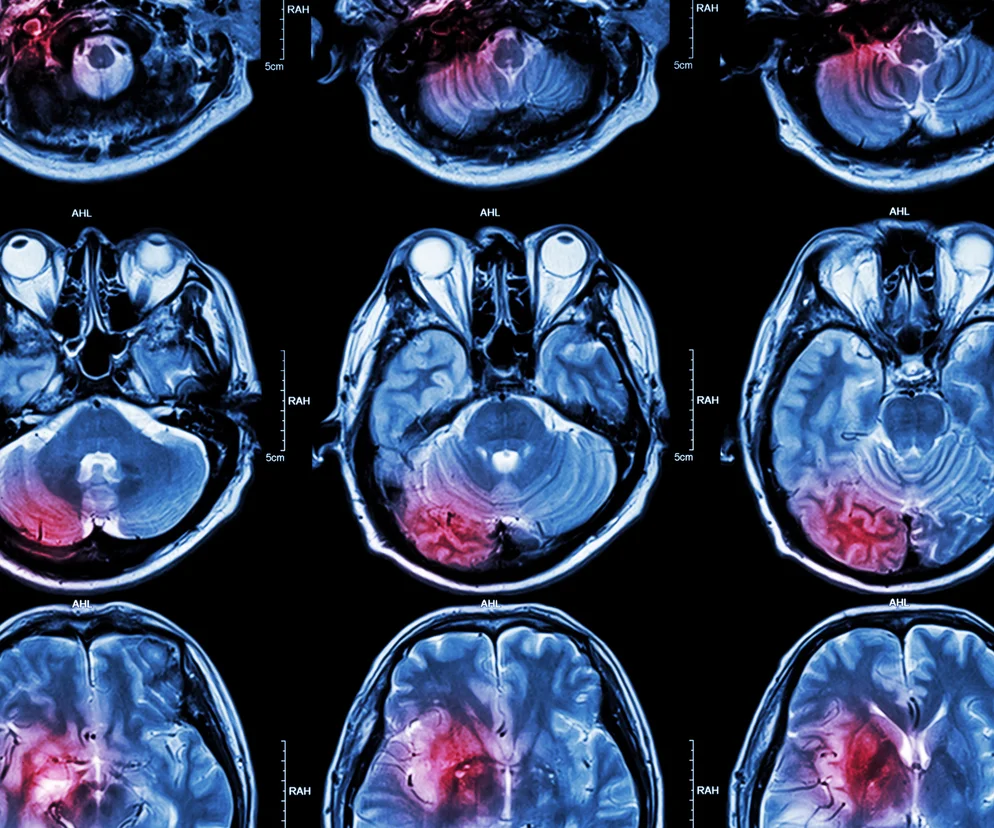

Udar mózgu - diagnostyka

Pacjent z udarem mózgu powinien trafić jak najszybciej na oddział neurologiczny, dysponujący tomografem komputerowym, aby w ciągu kilku godzin otrzymać specjalistyczną pomoc. Badanie tomograficzne jest niezwykle ważne, ponieważ pozwala zobaczyć obszar mózgu dotknięty choroba i określić jej rodzaj. Jeśli nie można wykonać tomografii, robi się punkcje lędźwiową, czyli pobiera specjalną igłą płyn mózgowo-rdzeniowy.

USG dopplerowskie pozwala ocenić stan tętnic szyjnych, które mogą być zablokowane przez zator. Sprawdza się również poziom krzepliwości krwi.

Jeżeli chory jest przytomny, wykonuje się też badanie neurologiczne (sprawdza się poprawność odruchów, ocenia siłę i sprawność mięśni, bada reakcje źrenic na światło). To wszystko pozwala precyzyjnie wyznaczyć obszar zniszczenia mózgu.

Na szpitalnym oddziale rehabilitacji neurologicznej (udarowym) pacjent jest poddawany szeregowi badań i testów, takich jak tomografia komputerowa (CT) czy rezonans magnetyczny (MRI), aby uzyskać jak najwięcej informacji na temat jego stanu zdrowia.